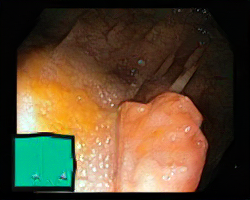

We have used a polyp dataset published with HyperKvasir dataset [51], which consists of polyp findings extracted from endoscopy examinations. HyperKvasir contains polyp images with corresponding segmentation masks annotated by medical experts. We use only this polyp dataset as a case study because of the time and resource-consuming training process of the SinGAN-Seg pipeline. However, the SinGAN-Seg model and pipeline can be used for any segmentation dataset.

A few sample images and the corresponding masks of the polyp dataset in HyperKvasir are shown in Fig 2. The polyp images are RGB images. The masks of the polyp images are single-channel images with white () for true pixels, which represent polyp regions, and black () for false pixels, which represent clean colon or background regions. In this dataset, there are different sizes of polyps. The distribution of polyp sizes as a percentage of the full image size is presented in the histogram plot in Fig 3, and we can observe that there are more relatively small polyps compared to larger polyps. Additionally, a subset of this dataset was used to prove that the performance of segmentation models trained with small datasets can be improved using our SinGAN-Seg pipeline, and the whole dataset was used to show the effect of using SinGAN-Seg generated synthetic images instead of a large dataset which has enough data to train segmentation models. In this regard, this dataset was used for two purposes: